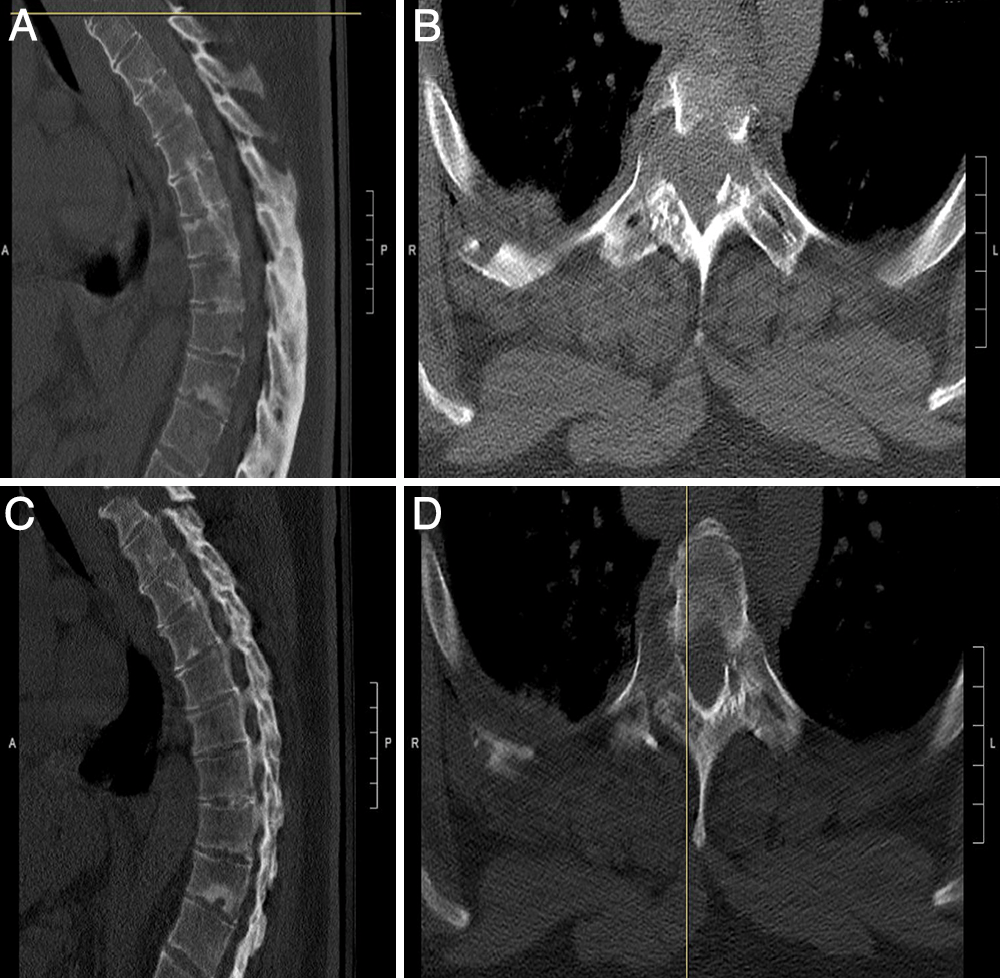

神外早8点手术有新译单一后路处理晚期强直性脊柱炎患者颈胸腰椎多节